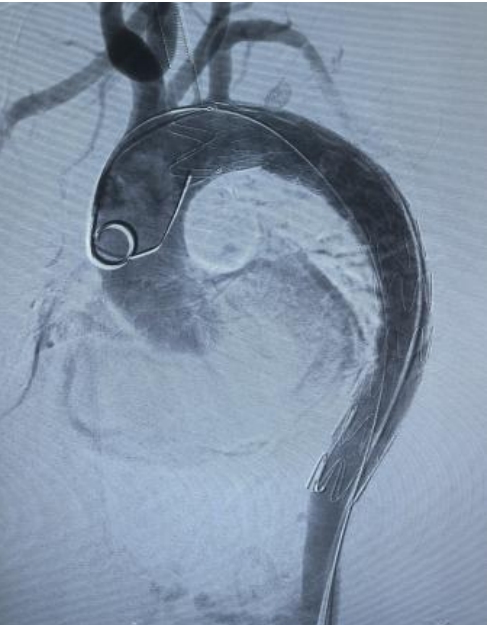

【放支架后实时】

术后患者血压控制显著改善;一周后复查显示支架定位精准、无移位无内漏,原先受累的肠系膜上动脉血流恢复通畅;术后第八天,患者康复情况良好,顺利出院,并将接受长期随访与血压管理。